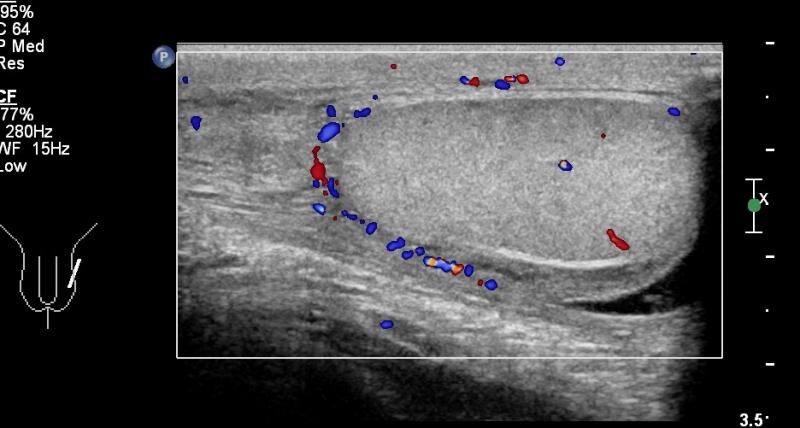

Przypadek 8: 16-latek z bólem moszny po stronie lewej od dnia poprzedniego. W badaniu przedmiotowym zaczerwienienie i niewielki obrzęk moszny po stronie lewej.

Rozpoznanie: W badaniu usg widoczne pogrubienie i przekrwienie najądrza lewego i osłonek jądra lewego. Nieco zwiększona ilość płynu w mosznie, płyn z licznymi przegrodami. Cechy stanu zapalnego najądrza lewego. Struktura obu jąder w normie.